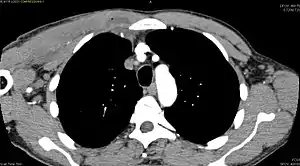

CT with IV contrast showing enlargement and heterogeneous hypodensity in the right pectoralis major muscle. A focal abscess collection with gas within it is present medially. There are enlarged axillary lymph nodes and some extension into the right hemithorax. Note the soft tissue and phlegmon surrounding the right internal mammary artery and vein. The patient was HIV+ and the pyomyositis is believed to be due to direct inoculation of the muscle related to parenteral drug abuse. The patient admitted to being a "pocket shooter"